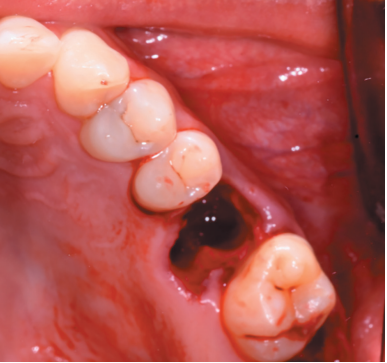

Aft er obtaining the informed consent, an anaestheti c block was performed using Arti caine 4% with Epinephrine 1:100,000 (UltracaineTM, Normon SL, Madrid, Spain) of the posterior and middle superior alveolar nerve, and anterior palati ne. An atraumati c extraction of the root remains of the 2.6 and the

curett age of the apical process (Figure 6) was performed, leaving the alveolus of the 2.6 prepared to receive the autotransplant of the 2.8 (Figure 7).

The 2.8 was then extracted with forceps (Figure 8), with minimal manipulati on of the periodontal ligament of the third molar, placing the upper third molar in the position of the upper fi rst molar (Figures 9 and 10).